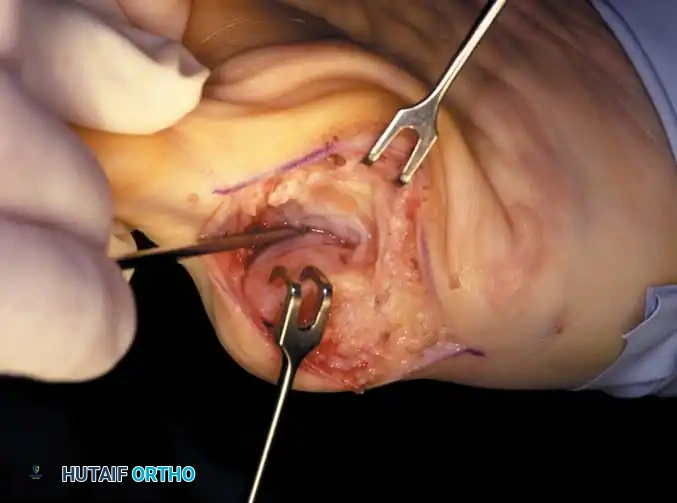

• Using a Freer elevator or a small osteotome for its strength, mobilize the fi bular sesamoid (Fig. 78-31A to C). This may be diffi cult in elderly patients with signifi cant deformity and adherence of the sesamoid to the metatarsal head. Lift the metatarsal dorsally for exposure (Fig. 78-31D and E).

Fig. 78-31 Excision of fi bular sesamoid in modifi ed Keller procedure. With base of proximal phalanx removed and medial eminence excision, exposure of fi bular sesamoid is not as diffi cult from medial incision. A, Operative photograph showing elevation of fi rst metatarsal with strong two-tooth retractor and use of small osteotome to mobilize fi bular sesamoid and lateral capsuloligamentous (frequently contracted) structures. Osteotome is between metatarsal head and lateral sesamoid. When mobilization of fi bular sesamoid is complete, entire sesamoid is visible for excision. Note chondromalacia of tibial sesamoid articular surface medial to osteotome. B, Fibular sesamoid has been excised, and lateral capsular structures and conjoined tendon (in forceps) have been released. Neurovascular bundle to lateral side of hallux is adjacent to these structures. C, Diagrammatic representation of modifi ed Keller procedure. By excising fi bular sesamoid, valgus moment of conjoined tendon of fl exor hallucis brevis and adductor hallucis no longer pulls fl exor hallucis longus tendon laterally (carrying hallux with it) through capsulosesamoid plantar plate and pulley system. D, Metatarsal head must be lifted dorsally to excise fi bular sesamoid under direct vision. E, Note exposure of fi bular sesamoid after mobilization of metatarsal head. Continued